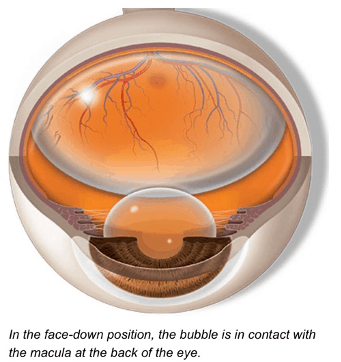

This surgery involves removal of the vitreous gel that is pulling on the retina. Often a gas bubble may be placed in the eye to keep the retina attached while healing takes place. When a gas bubble is introduced, you may need to keep your head in a certain position for a time. Also you will not be able to fly for a period of time as the high altitudes can cause dangerous increase in eye pressure from expansion of the gas bubble. Over time, the gas bubble will gradually be replaced by your own body’s fluids.

Sometimes, an oil bubble may be introduced instead of a gas bubble. An oil bubble will need to be removed later when the retina has fully attached.

What is the treatment for macular holes?

After macular hole surgery:

- You will need to keep a face down position for most of the day for a week or more. This is so that the gas bubble will float up against the macular and stay in position for the macular hole to close properly.

- Air travel, mountain climbing and diving should be avoided as this may cause the gas bubble to expand resulting in eye pressure problems.

- Vision will be blur immediately after surgery due to the gas bubble. Over time, vision will improve as the gas bubble reduces and healing of the macular hole occurs. The amount of vision you get back also depends on the size of the hole and the length of time the hole was present before surgery.